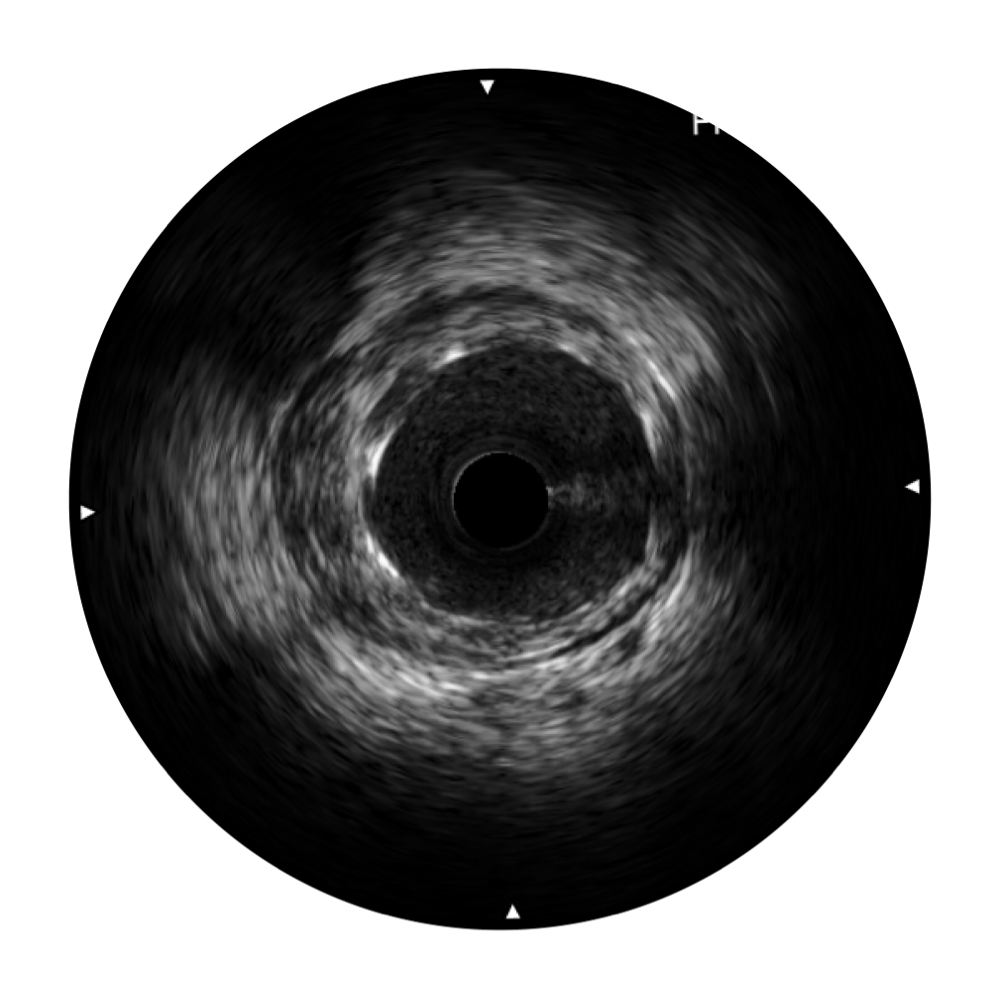

• 亚星官网宽频IVUS图像

对比传统IVUS导管成像,亚星官网宽频IVUS图像的近场支架梁显影更细腻,远场中膜外血管仍清晰可辨,兼顾远中近,兼顾分辨力与穿透深度